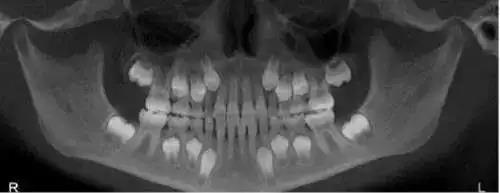

儿童乳牙以下的就是恒牙牙胚

当小朋友还在妈妈肚子里的时候,牙胚就已经发育好了,到了一定的时间,就会自行萌出(男宝宝出牙会比女宝宝晚一点哦)。